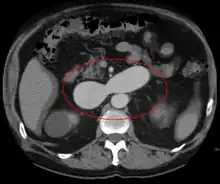

- Computerized tomography (CT) scan is a noninvasive X-ray to view the anatomical structures within the brain to detect blood in or around the brain. A newer technology called CT angiography involves the injection of contrast into the blood stream to view the arteries of the brain. This type of test provides the best pictures of blood vessels through angiography and soft tissues through CT.

AVMs can occur in various parts of the body:

- spleen[12]